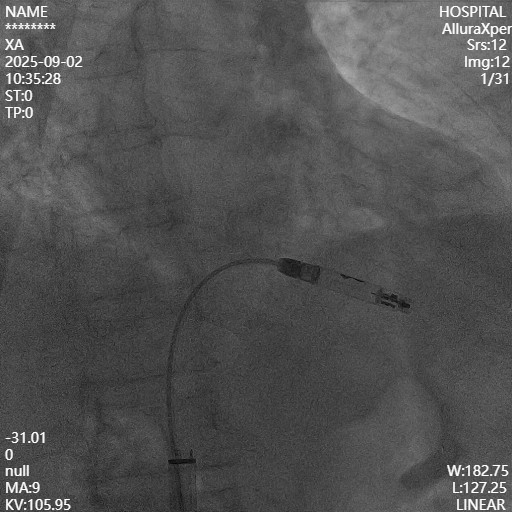

CEGM显示损坏明显抬高约3mV,测得阈值1.25V,感知4.4mV,阻抗530Ω。

参数良好,满足固定要求!

最终完美固定并释放起搏器!

释放后参数结果非常优秀!